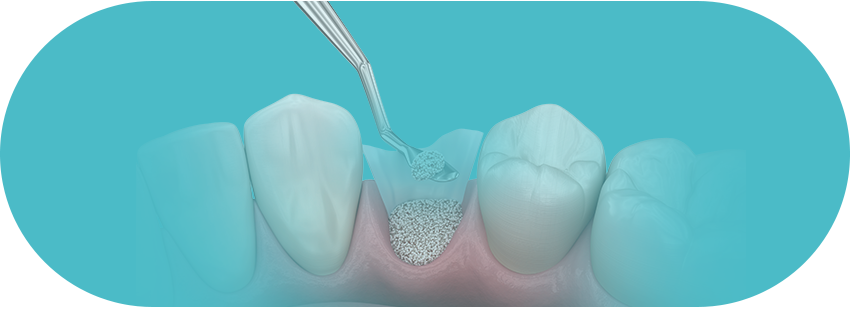

뼈이식 임플란트

고난도 뼈이식술은 치과의사의

경험이 매우 중요합니다.

걱정하지 마세요!

잇몸뼈 부족으로

임플란트 치료가 불가능

하다고만 설명 들으셨나요?

풍부한 임상경험과 노하우로

뼈가 부족한 경우, 고혈압, 당뇨, 전신질환이 있어도

자신있습니다!